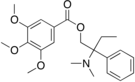

The pharmacodynamic response to an opioid depends upon the receptor to which it binds, its affinity for that receptor, and whether the opioid is an agonist or an antagonist. For example, the supraspinal analgesic properties of the opioid agonist morphine are mediated by activation of the μ1 receptor; respiratory depression and physical dependence by the μ2 receptor; and sedation and spinal analgesia by the κ receptor. Each group of opioid receptors elicits a distinct set of neurological responses, with the receptor subtypes (such as μ1 and μ2 for example) providing even more [measurably] specific responses. Unique to each opioid is its distinct binding affinity to the various classes of opioid receptors (e.g. the μ, κ, and δ opioid receptors are activated at different magnitudes according to the specific receptor binding affinities of the opioid). For example, the opiate alkaloid morphine exhibits high-affinity binding to the μ-opioid receptor, while ketazocine exhibits high affinity to ĸ receptors. It is this combinatorial mechanism that allows for such a wide class of opioids and molecular designs to exist, each with its own unique effect profile. Their individual molecular structure is also responsible for their different duration of action, whereby metabolic breakdown (such as N-dealkylation) is responsible for opioid metabolism.

Phenylpiperidines

- Pethidine (meperidine)